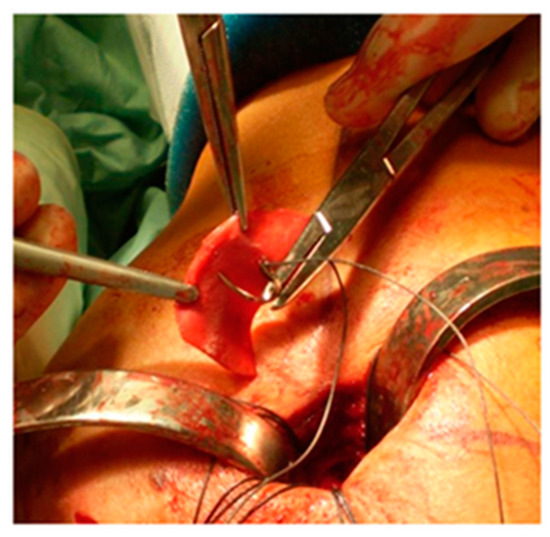

The edges of the RC tear were identified and debrided; tendon mobilization was attempted to verify if a primary tendon-to-bone repair was possible. When re-insertion to the footprint was possible, but the tendon tissue quality was clinically considered poor, a patch was sutured with non-absorbable stitches on the bursal side of the RC and reinserted together with the tendon onto the respective tuberosity over the anchors (Figure 1). The RC tendon was retracted and non-mobilizable, confirming the impossibility of a direct tendon-to-bone repair sutured to the edges of the tendon stump with non-absorbable sutures and then reinserted into the tuberosity with anchors (Figure 2). In both techniques (augmentation and bridging), and with both the biological implant (xenograft of collagen of porcine origin and DED-LYO allograft), the patch was cut to the appropriate size corresponding to the gap to be reinforced or covered. To control bleeding, in the absence of contraindications, tranexamic acid was administered both intravenously and locally, as previously described [17].

Figure 1. DED-LYO patch augmentation procedure.